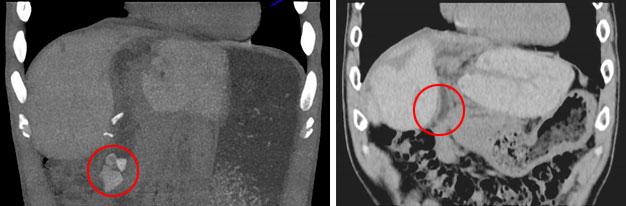

术前:胆总管多发结石 术后:结石已去除